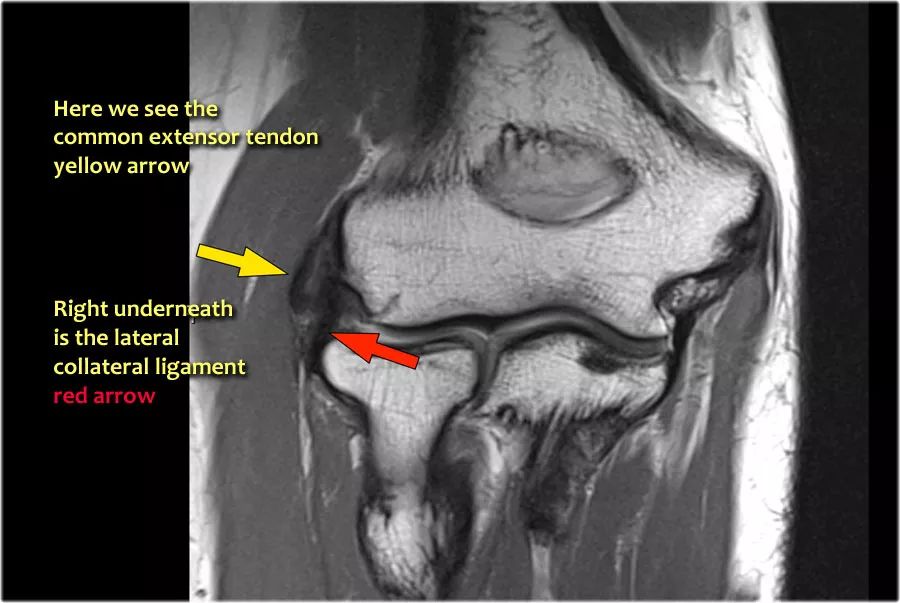

1.外上髁炎外上髁炎也称为网球肘,但在95%的病例中,非网球运动员可以看到。这是由于常见伸肌腱的慢性应激,导致部分撕裂和肌腱变性。通常,桡侧腕伸肌是所涉及的组成部分。在更严重的情况下,LCL会撕裂,这对保守治疗的反应很差。

下面是一个典型案例。T1和T2W图像上都有增厚和异常的内在信号。